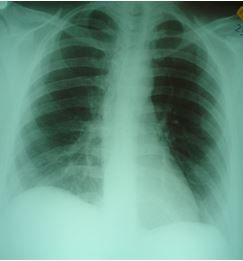

Case 3: The third woman was referred to the ED by her pain specialist. She had “refractory” right flank and abdominal pain that had not been relieved by a cholecystectomy: the plan was to do an intercostal rib block Monday in the office. The pain is in the right flank and worse with inspiration and twisting movement or lying on her side. She also has had a cough productive of yellow phlegm and occasional blood, which she had been told was due bronchitis for which she recently finished a course of antibiotic. Her chest x-ray is shown (Figure).